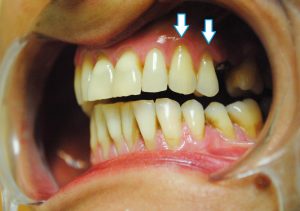

Os mostramos uno de los casos tratados recientemente en nuestra clínica dental. Esta es la imagen que presentaba la boca de nuestro paciente antes de comenzar con los tratamientos:

Se observan en la imagen, indicadas con flechas, dos recesiones de encía en el segundo cuadrante, además de la ausencia de una pieza que se solucionó también con implante dental unitario de carga inmediata.